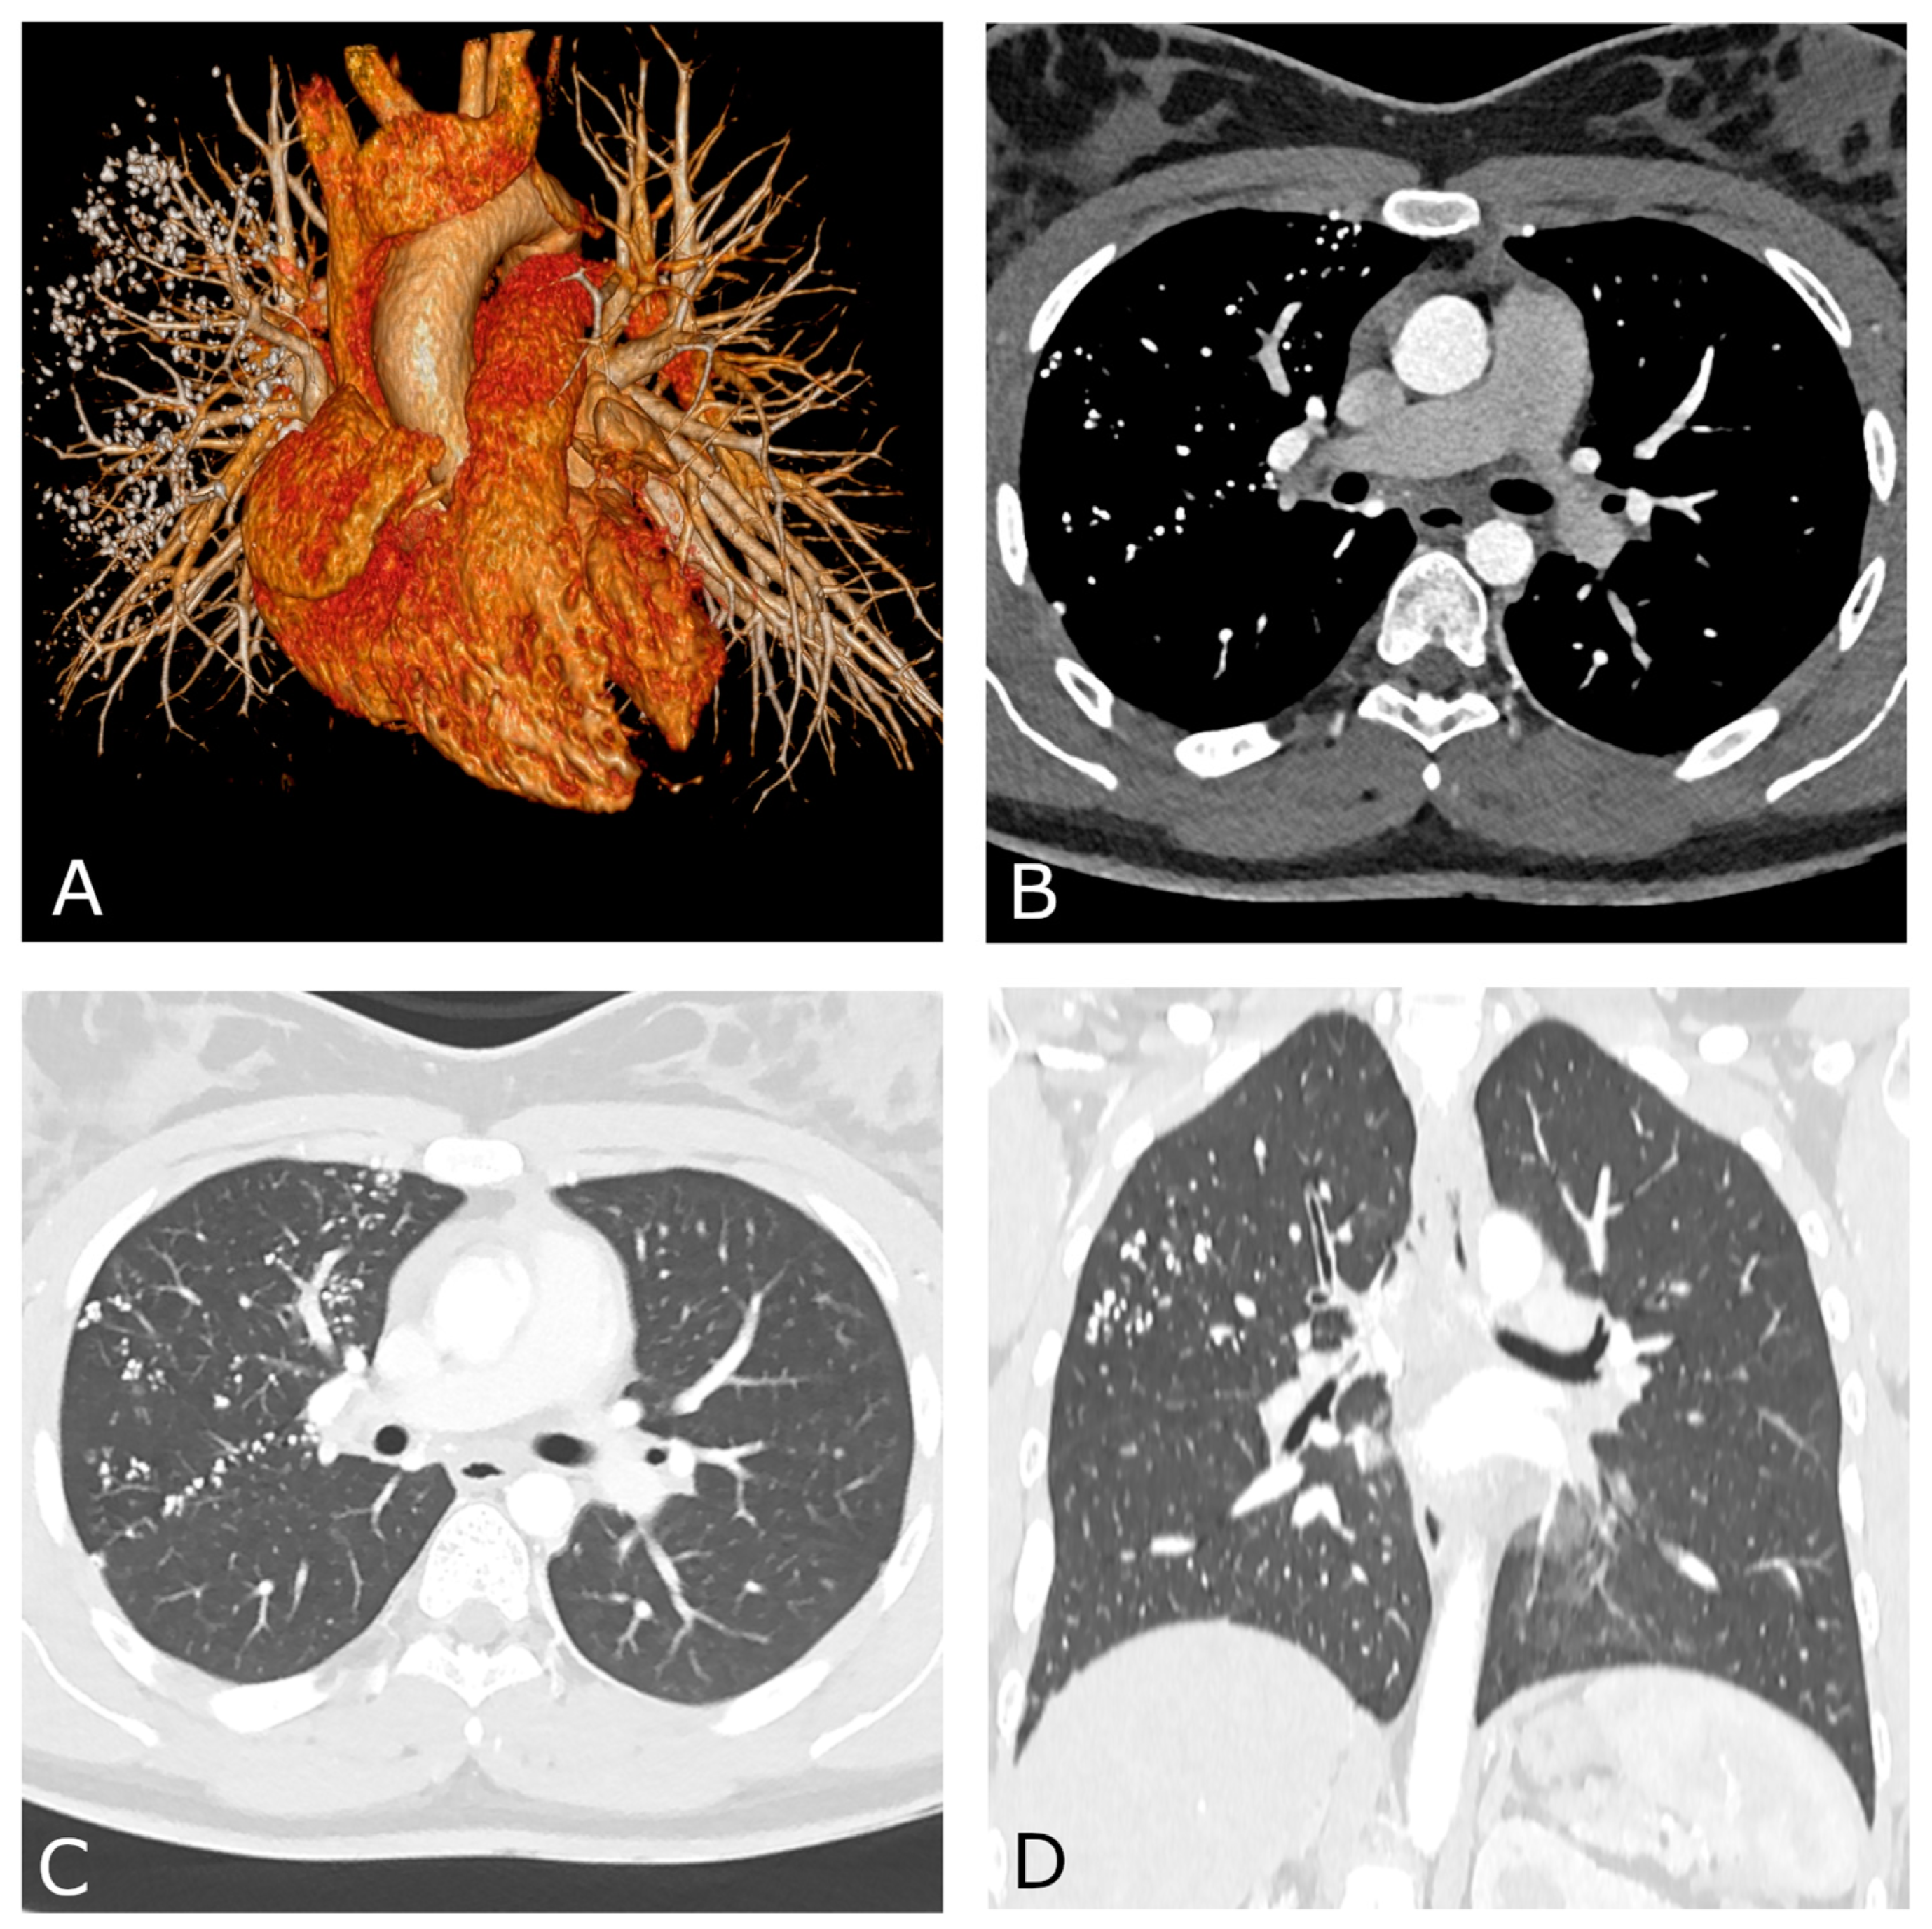

A 17-year-old female, with a history of surgical treatment for congenital Type C esophageal atresia at birth, and a diagnosis of distal tracheoesophageal fistula (TEF) relapse, came to us for observation for pre-operative planning. The patient had mild dysphagia to solid foods but was otherwise healthy. She did not have respiratory symptoms or coughing during meals. Chest CT angiography (CTA) with ECG triggering was performed to exclude any congenital cardiovascular abnormalities prior to surgery. The patient received 1.2 mL/kg body weight of intravenous nonionic contrast medium (Iomeron 400, Bracco, Milan, Italy) followed by 40 cc of diluted contrast bolus, using a power injector system at a rate of 5 mL/s through an 18-gauge i.v. catheter placed in the right arm. The scan was performed on a dual-layer dual-energy CT (DECT) platform (IQon Spectral CT, Philips Healthcare, Best, The Netherlands) only during the arterial phase, to minimize the radiation exposure. Chest CTA did not reveal any cardiovascular abnormalities. As a collateral finding, multiple high-density foci were noted within the right lung (Figure 1). They were located in almost all segments of the right upper lobe and in the middle lobe with a mainly perylimphatic distribution. These lesions were partly confluent and ranged in size from 1 to 6 mm. Moreover, confined “tree-in-bud” opacities and thickened interlobar septa were also noted. No signs of bronchial distortions, honeycombing or other fibrotic-like changes were present.

Figure 1.

Chest CT angiography with ECG gating performed on a dual-layer DECT platform. Volume-rendering reconstruction (A) shows normal cardiovascular anatomy with multiple high-density foci within the right lung. Both axial (B,C) and coronal reconstructions (D) demonstrate the typical perilymphatic distribution of the lung nodules. Mediastinal (B) and lung parenchyma (C) views performed along the same axial plane are shown.